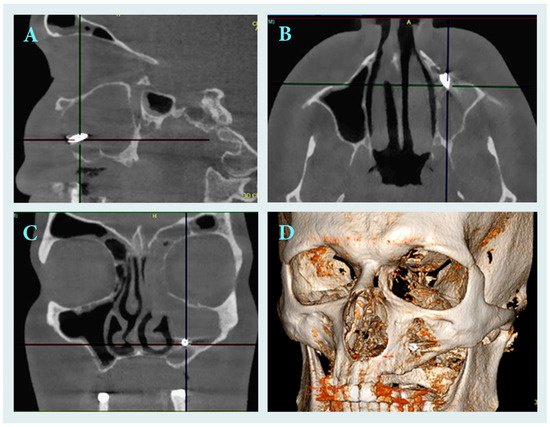

Serratia marcescens Maxillary Sinusitis and Ethmoiditis in an HIV-Positive Patient Caused by Dental Implant Migrating into the Maxillary Sinus

Iatrogenic maxillary sinusitis accounts for a significant proportion of unilateral sinus infections. This report describes a 36-year-old HIV-positive patient with Serratia marcescens chronic left maxillary sinusitis and ethmoiditis caused by migration of a dental implant into the maxillary sinus. The implant was successfully [...] Read more.

Iatrogenic maxillary sinusitis accounts for a significant proportion of unilateral sinus infections. This report describes a 36-year-old HIV-positive patient with Serratia marcescens chronic left maxillary sinusitis and ethmoiditis caused by migration of a dental implant into the maxillary sinus. The implant was successfully removed endoscopically via functional endoscopic sinus surgery. Histopathological examination revealed polypoid mucosa with chronic inflammation, while microbiological culture grew Serratia marcescens, an uncommon and opportunistic pathogen. Targeted antibiotic therapy with trimethoprim/sulfamethoxazole was administered for 20 days. Six-month follow-up revealed complete remission without recurrence of sinusitis. Full article